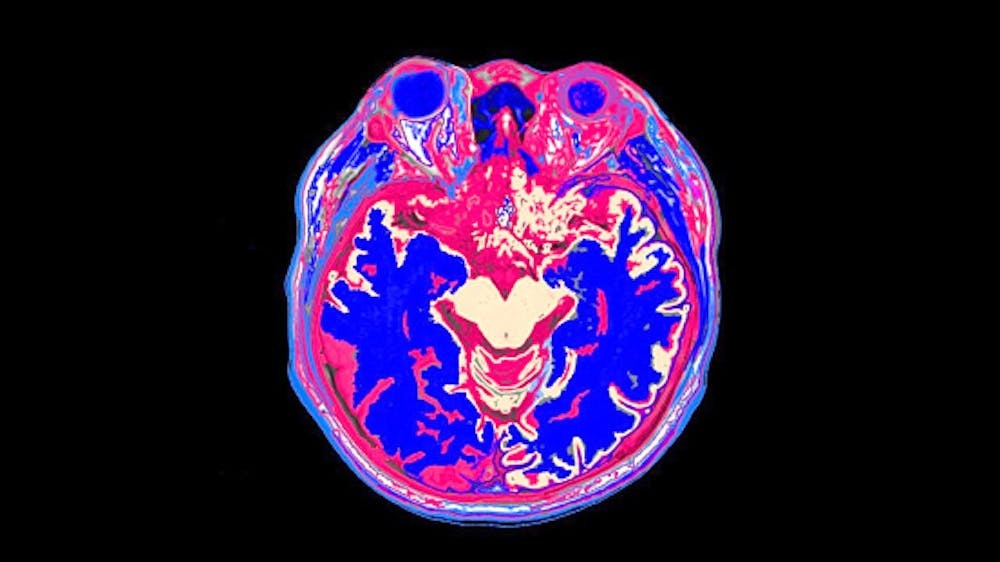

Как учёный-языковед, я изучаю, как биологические факторы и социальный опыт формируют язык. Моя работа исследует, как мозг обрабатывает устную и письменную речь, используя такие инструменты, как МРТ и ЭЭГ.

Ваш мозг использует одни и те же языковые и когнитивные системы как при чтении, так и при прослушивании, но при этом выполняет разные функции в зависимости от того, как вы воспринимаете информацию.

Когда вы читаете, ваш мозг напряжённо работает на фоне. Он распознаёт формы букв, сопоставляет их со звуками речи, соединяет эти звуки со смыслом, а затем связывает эти смыслы между словами, предложениями и даже целыми книгами. В тексте используется визуальная структура, например знаки препинания, разрывы абзацев или выделенные жирным шрифтом слова, чтобы направлять ваше понимание. Вы можете двигаться со своей скоростью.

Слушание, напротив, требует, чтобы ваш мозг работал в темпе говорящего. Поскольку разговорная речь обычно быстрее, слушателям приходится полагаться на когнитивные процессы, включая память, чтобы удержать в памяти только что услышанное.

Речь также представляет собой непрерывный поток, а не чётко разделённые слова. Когда кто-то говорит, звуки смешиваются в процессе, называемом коартикуляцией. Это требует от мозга слушателя быстро определять границы слов и связывать звуки со смыслом. Помимо распознавания самих слов, мозг слушателя также должен обращать внимание на тон, личность говорящего и контекст, чтобы понять смысл речи.

Понимание на слух и чтение будут более похожими друг на друга для простых повествований, таких как вымышленные истории, чем для нехудожественных книг или эссе, в которых объясняются факты, идеи или принципы работы вещей. Мои исследования показывают, что жанр влияет на то, как вы читаете. На самом деле, разные виды текстов опираются на разные специализированные сети мозга. Вымышленные истории задействуют участки мозга, связанные с социальным пониманием и рассказыванием историй. Нехудожественные тексты, с другой стороны, опираются на сеть мозга, которая помогает нам мыслить стратегически и направлять внимание на конкретную цель.